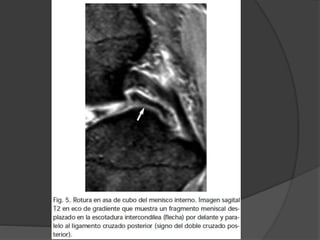

 Asa de cubo: fragmento interno desplazado en la

escotadura intercondílea

○ Las roturas del menisco interno en asa tipicamente se

localizan bajo el LCP= signo doble LCP

 Forma:  Picode loro, rotura oblicua con una orientación radial en el borde libre meniscal con un trayecto paralelo al eje del menisco cuando se extiende perifericamente  Mixtas: forma de estrella  Asa de cubo: fragmento interno desplazado en la escotadura intercondílea ○ Los fragmentos menores de un tercio del menisco, pueden no ser detectados ○ Las roturas del menisco interno en asa tipicamente se localizan bajo el LCP= signo doble LCP ○ Diferenciar de :LCA roto, ligamento meniscofemoral roto, fragmento libre en la escotadura intercondílea